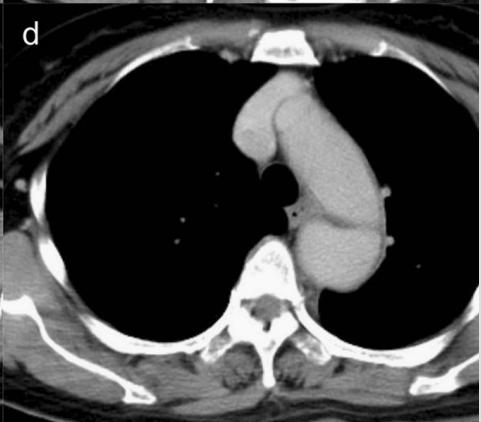

下图的胸部CT平扫,有什么致命的问题?

血管壁钙化啊,老年人很常见啊,

注意,看下面,钙化在血管的里面,不是在管壁!难道是血液钙化了?血液钙化?

这不是血液钙化,这是主动脉夹层导致的血管钙化内移!血液不会钙化,因为动脉夹层,导致钙化的内膜被压迫进入血管!

增强CT一看,就一清二楚了!